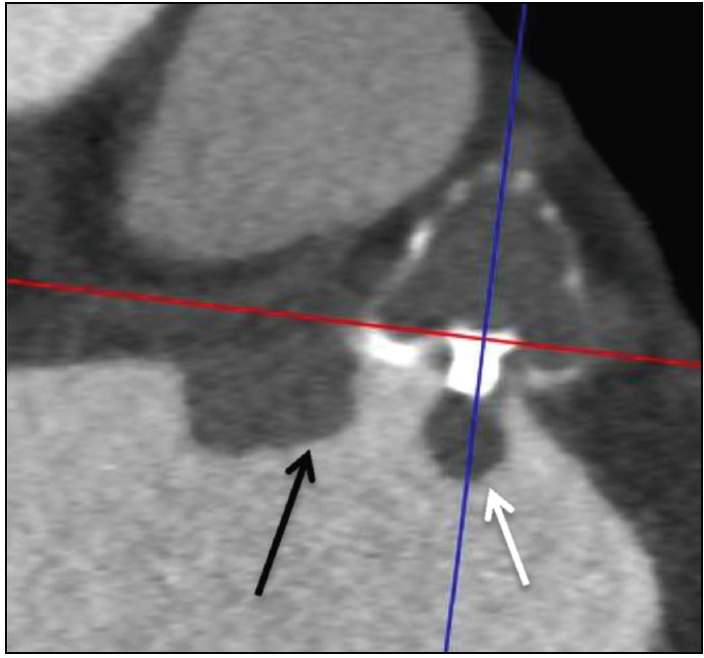

Figure 1. Contrast-enhanced CT images revealing an atrialside device thrombus on a Watchman device at the fabric insert (white arrow) and adjacent to the device (black arrow). Reprinted from Saw J, Fahmy P, DeJong P, et al. Cardiac CT angiography for device surveillance after endovascular left atrial appendage closure. Eur Heart J Cardiovasc Imaging. 2015;16:1198–1206, by permission of Oxford University Press.

After LAA closure with the Watchman device, thrombosis may appear on the surface of the device. The implantation of thrombogenic devices in patients with nonvalvular AF who are at high risk of thrombosis in the left atrium requires antithrombotic therapy to prevent on-device thrombus formation (Figure 1). Ideally, antithrombotic therapy should be pursued until complete occluder endothelialization occurs. Based on the postimplantation treatment protocols from the PROTECT AF and PREVAIL trials, the vast majority of Watchman implantations described in the literature were accompanied by warfarin anticoagulation for 45 days, followed by dual antiplatelet therapy (DAPT) for 6 months postprocedure and aspirin thereafter.